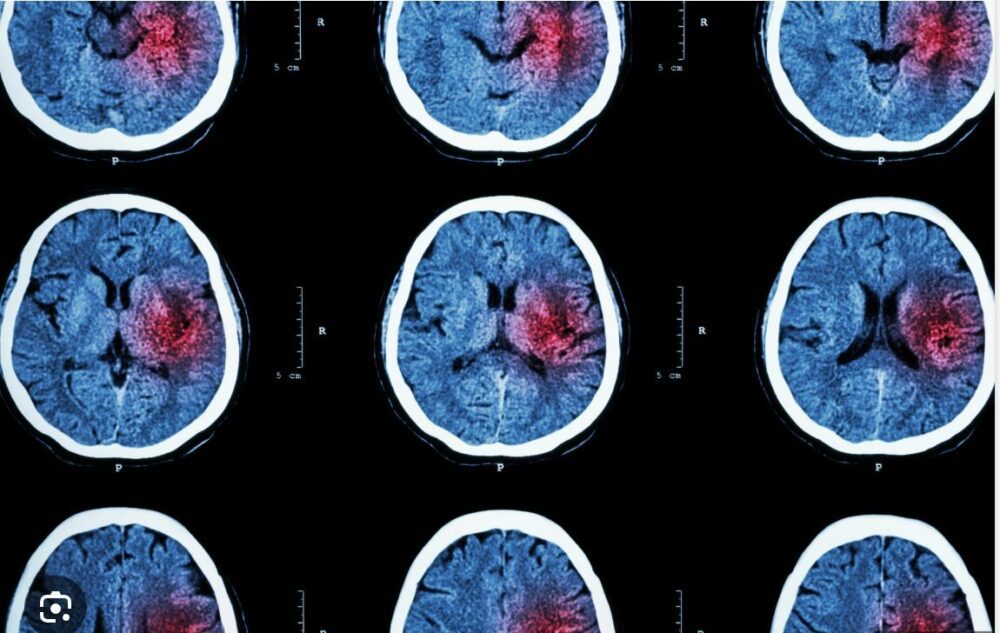

Esta patología neurológica se produce por una alteración del flujo sanguíneo que provoca daños graves en el tejido cerebral por falta de oxígeno y nutrientes. “El cerebro es particularmente sensible a la falta de irrigación –explica Pablo Ioli, presidente de la Sociedad Neurológica Argentina–. En total, pesa alrededor de un kilo y medio, representa el 2% del peso corporal, pero consume el 20 o 25% de nuestra energía. En proporción, necesita mucho oxígeno y mucha glucosa para funcionar. En el momento en que deja de recibirlos por una obstrucción (con un coágulo, en el 80 al 85% de los casos, o por una hemorragia), comienzan a perderse neuronas rápidamente. Se estima que mueren dos millones por minuto, de modo que en poco tiempo se puede producir un daño irreversible. El territorio afectado depende del tamaño del bloqueo. Hay ACV muy pequeños que ocasionan déficits neurológicos menores y se recuperan en un lapso breve, pero cuando se tapa una arteria muy grande, se ven otros extensos, con mucho tejido cerebral afectado y daño neurológico”.